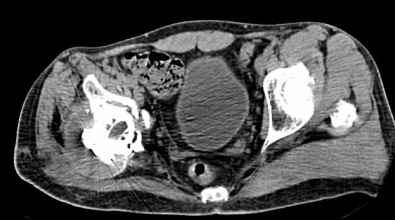

Мужчина, 45 лет. 6 мес. назад перенес тотальное эндопротезирование правого тазобедренного сустава по поводу ложного сустава шейки бедра.

Характер реконструкции вертлужной впадины не известен. Через 3 мес. после операции отметил щелчки и хруст при движениях в области эндопротеза. В анамнезе туберкулез легких. Сейчас, по заключению фтизиатра, в легких активного процесса нет. Местного воспаления нет.Предполагается нестабильность чашки в связи с бактериальным воспалением. Планируется удаление чашки и цемента, пластика дна измельченными аутотрансплантами и гидроксилапатитной керамикой, затем кольцо Мюллер, цементная чашка.

Мне кажется, что необходимо сначала выполнить пункцию, и принимать решение о тактике - исходя из результатов посева полученного пунктата.

И еще, в случае одномоментного реэндопротезирования здесь показана имплантация кольца Бур-Шнайдера (ИМХО)

прямо скажем, очень загадочная конструкция с проволокой и винтами. :) На основании чего Вы подозреваете септическую нестабильность? Каковы результаты анализов? Согласен с доктором - нужно сделать пункцию. Есть ли снимки до и сразу после операции? Знаете ли Вы диаметр головки,какой будет внутренний диаметр Вашей чашки? Известно ли, чей протез? Может есть смысл найти автора работы и узнать о подробностях установки протеза?